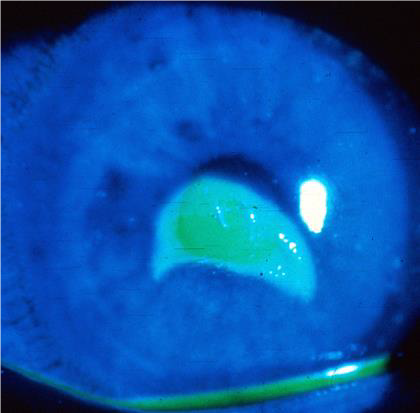

Figures: Corneal abrasion.

Figure 19. Epithelial defect with NO infiltrate. Photo credit: CAPT (Ret) Joseph Pasternak, MD.

Figure 20. Epithelial defect stains with fluorescein when illuminated with cobalt blue light. Photo credit: CAPT (Ret) Joseph Pasternak, MD.